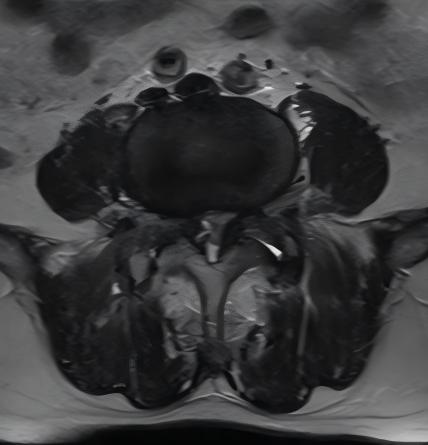

术前

术后